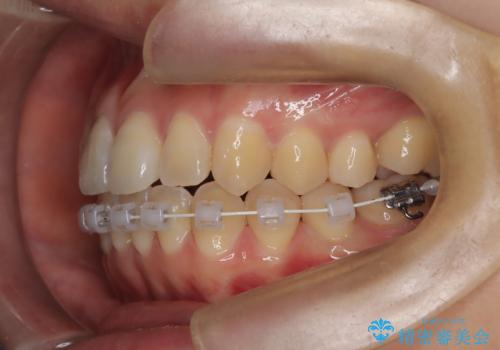

- 矯正装置

- 審美装置

- 治療期間

- 1年6ヶ月

- 治療回数

- 10-30回